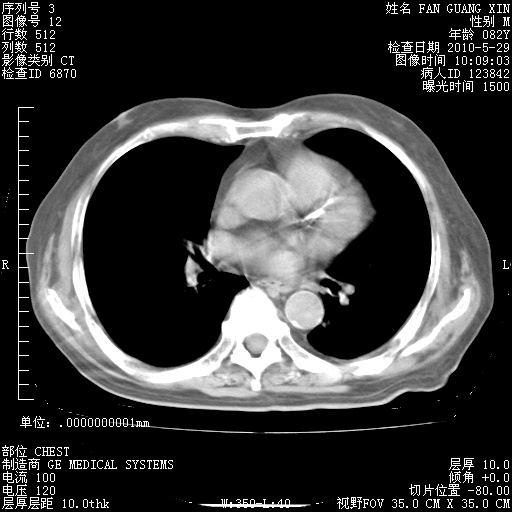

治疗3周后的肺部CT纵隔窗

再治疗10天后的肺部CT 纵膈窗

阅读此次胸部CT,肺间质渗出性改变较入院时有吸收。目前从体温、白细胞、中性分叶明显增高,肯定存在细菌感染(发生医院感染哦,若无消化道及泌尿系统等感染的依据,肺部感染可能大)。若你院头孢哌酮舒巴坦钠耐药率较高,同意你的方案,若48小时体温仍高,可考虑使用碳青霉稀类抗菌药物,同时可予超声雾化、注意滴数时加大液体量。白蛋白33.30g/L较低哦,需加强营养等支持治疗。